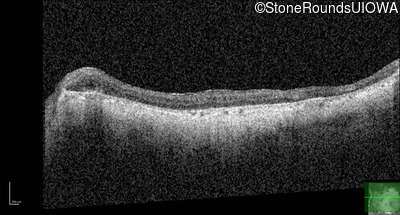

Optical Coherence Tomography - Right - 10/225 sc

Exemplar / OCT Stack

OCT Stack